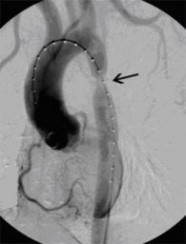

Aortenkoarktationsstenose nach Stentimplantation

(Bild 2 von 4)